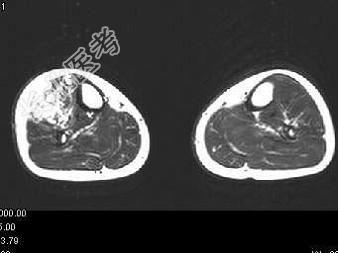

- 单项选择题男,15岁, 小时候发现左下肢肿胀,曾多次出血, 结合图像,最可能的诊断是 ( )

C、下肢血管瘤